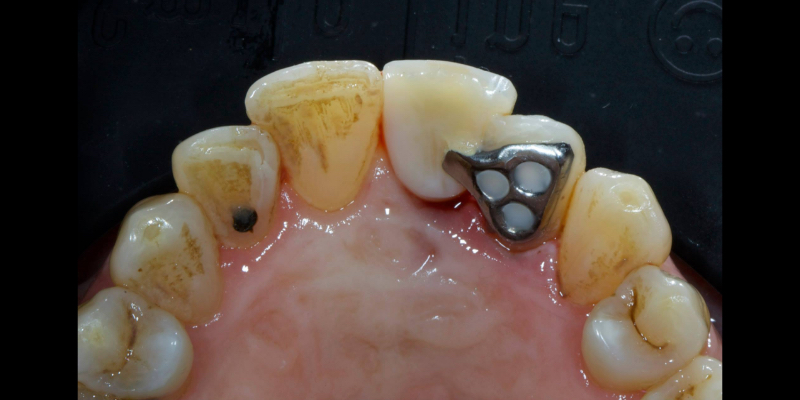

If a fixed adhesive provisional is employed, a good approach is to use a Rochette-type nonprecious bridge with three holes in the wing. This is retained by simply etching into the holes, rinsing, drying, and placing three separate increments of paste composite.

The composite can be easily removed with a bur and popping off the wing with a sharp curette. It is desirable to use a nonstrategic tooth (i.e., not the tooth that is planned to be the final abutment) as the abutment for the provisional, since minor changes to the palatal contour caused by bonding and removing the provisional may result in a suboptimal fit of the final prosthesis. The pontic is typically fabricated from acrylic or composite because this is more economical and easier to add to and modify when contouring the soft tissue.

Here’s Elizabeth’s case. She had a periodontal lesion affecting the upper right central incisor (Fig. 13).

The tooth was extracted and a provisional nonprecious adhesive bridge with composite pontic was placed (Figs. 14-16).

The Rochette-type wing was placed on the lateral incisor abutment (Fig. 17). Grafting procedures were carried out before definitive restoration with a lithium disilicate adhesive bridge.